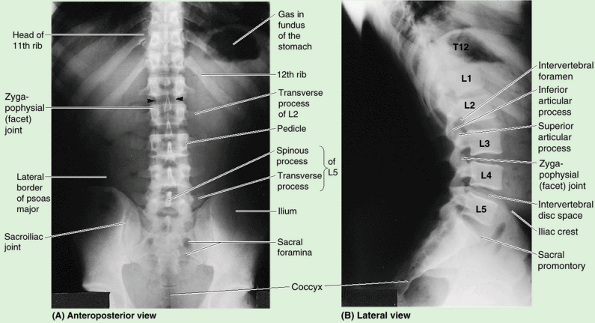

Because the weight they support increases toward the inferior end of

the vertebral column, lumbar vertebrae have massive bodies, accounting

for much of the thickness of the lower trunk in the median plane. Their

articular processes extend vertically, with articular facets sagittally

oriented initially (beginning abruptly with the T12–L1 joints) but

becoming more coronally oriented as the column descends. The L5–S1

facets are distinctly coronal in orientation. In the more sagittally

oriented superior joints, the laterally facing facets of the inferior

processes of the vertebra above are “gripped” by the medially facing

facets of the superior processes of the vertebra below, in a manner

that facilitates flexion and extension, allows lateral flexion, but

prohibits rotation (Figs. 4.1 and 4.2).

The transverse processes project somewhat posterosuperiorly as well as

laterally. On the posterior surface of the base of each transverse

process is a small accessory process,

which provides an attachment for the medial intertransverse lumborum

muscle. On the posterior surface of the superior articular processes

are mammillary processes, which give attachment to the multifidus and medial intertransverse muscles (back muscles).

carries the weight of the whole upper body. L5 is distinguished by its

massive body and transverse processes. Its body is markedly deeper

anteriorly; therefore, it is largely responsible for the lumbosacral

angle between the long axis of the lumbar region of the vertebral

column and that of the sacrum (Fig. 4.1D). Body weight is transmitted from L5 vertebra to the base of the sacrum, formed by the superior surface of S1 vertebra (Fig. 4.5A).